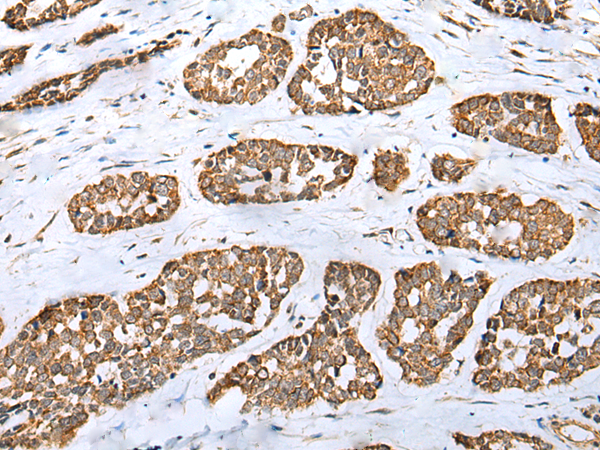

IHC positive control: |

Human esophagus cancer |